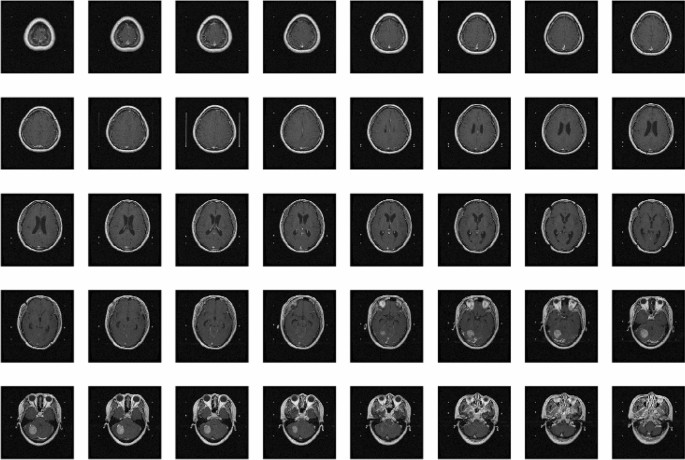

The dataset of MRIs were originally acquired for guiding radiosurgical treatment using the Gamma Knife from 1999 to 2018. This dataset contained 556 patients suffered from intracranial metastases and referred for GKRS, including the precise lesion locations of total 1872 metastases lesions had been collected. This retrospective study was approved, and informed consent was waived by the Institutional Review Board of Taipei Veterans General Hospital (IRB-TPEVGH No.: 2017-10-017AC) and conformed to the tenets of the Declaration of Helsinki. All methods were carried out in accordance with relevant guidelines from IRB-TPEVGH. This article investigated tumors with a volume greater than 0.15 ml. In Fig. 1, the reason is that the size of the tumor accounts for almost half of the total number of tumors. A total of 492 patients with 904 tumors and 23354 \(T_{1}\)-weighted MRI images were found that an average of 48 images per patient, \(20\%\) of which had tumors, showed an imbalanced dataset. The image format is stored with the size of \(512\times 512\) pixels (approximately 5 mm per pixel) and the thickness of 3 mm. The original image of the whole brain in per patient will be presented in Fig. 2. In order to generate a corresponding mask for each image to use in the calculation of tumor volume, several DICOM tags need to be used.

Post-contrast T1-weighted MRI per patient.